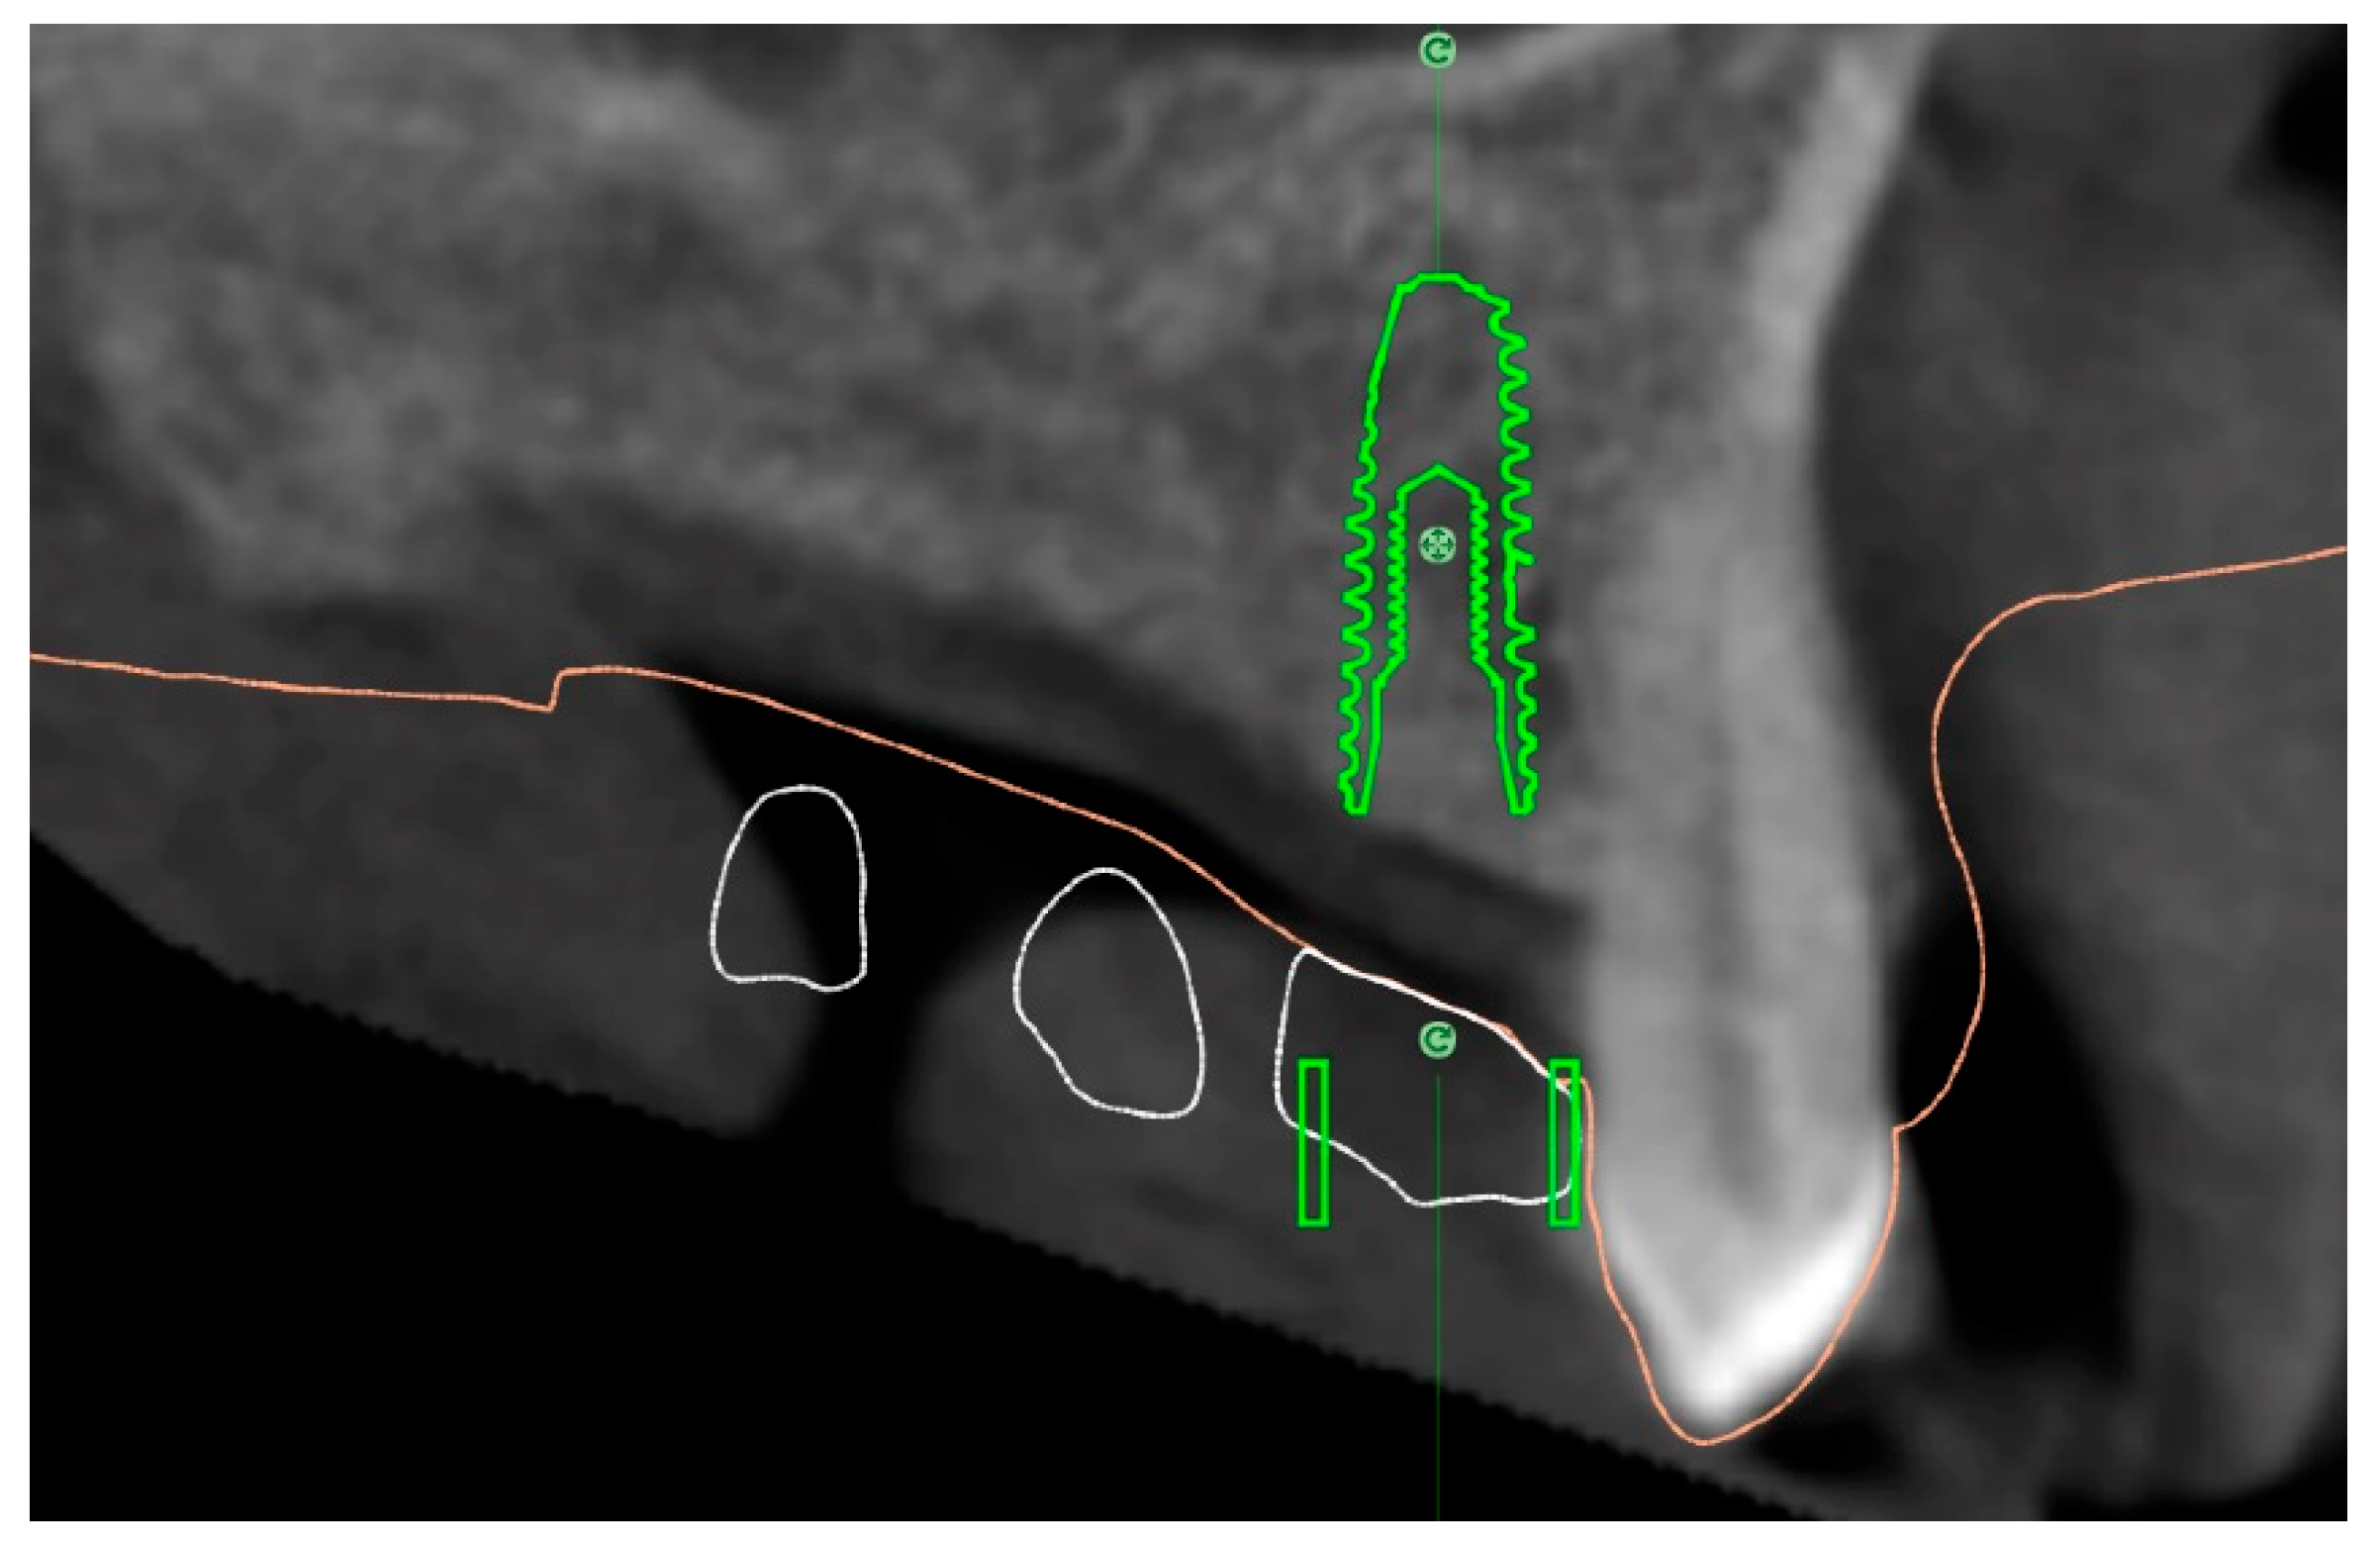

Enrolled patients received preoperative photographs, periapical radiographs or panoramic x-rays for initial screening and evaluation. The prosthetic-driven planning workflow started by taking a cone beam computed tomography (CBCT) scan (Cranex 3Dx, Soredex, Tuusula, Finland) by using a wax bite to separate dental arches. Then, the patients received intraoral digital impression taken using the 3M True Definition Scanner (3M Italia, Pioltello, Milano). The digital data (STL, Surface Tessellation Language) were imported in a 3D design software (exocad DentalCAD, Exocad GmbH, Darmstadt, Germany) to realize a virtual wax-up according to the functional and esthetic requirements. Then, the STL and DICOM (Digital Imaging and COmmunications in Medicine) data were imported in a 3D software planning program (3Diagnosys ver. 5.0, 3DIEMME srl, Cantù, Italy). Then, the reprocessed surface extrapolated from the DICOM data (by using a Hounsfield scale filter) and the surface generated by the master cast scanning process, or by the intraoral scanning process, were merged with the best-fitting repositioning tools of the software (3Diagnosys ver. 5.0, 3DIEMME srl). Afterwards, prosthetic-driven implants/abutments size and location were planned to take into account the bone quality and quantity, soft tissue thickness, anatomical landmarks, as well as type, volume, and shape of the final restoration. After careful functional and esthetic evaluation and final verification, the prosthetic-driven plan was approved. At this point, patients were randomly assigned to receive conventional stereolithographic surgical template with (control group, Figure 1) or without (test group, Figure 2 and Figure 3) metallic sleeves. Stereolithographic surgical templates were designed and fabricated by an independent certified center not previously involved in the study (New Ancorvis srl, Bargellino, Italy). In the test group, conventional templates with close-sleeve-design were produced to place implants between premolars. In case of implants to be placed in molar area, template with open sites were produced to solve interarch space limits.

Accuracy: Three deviation parameters (horizontal, vertical, and angular) were defined and calculated between the planned and placed implant positions according to a previously published study [7]. An expert mechanical engineer (FC) not previously involved in the study, performed all the measurements (Figure 4 and Figure 5).

Figure 4.

Superimposition of the Surface Tessellation Language (STL) derived from the planning with the STL taken after implant placement.

Figure 5.

Measurement of the virtual planning accuracy by superimposition of the STL derived from the planning with the STL taken after implant placement.